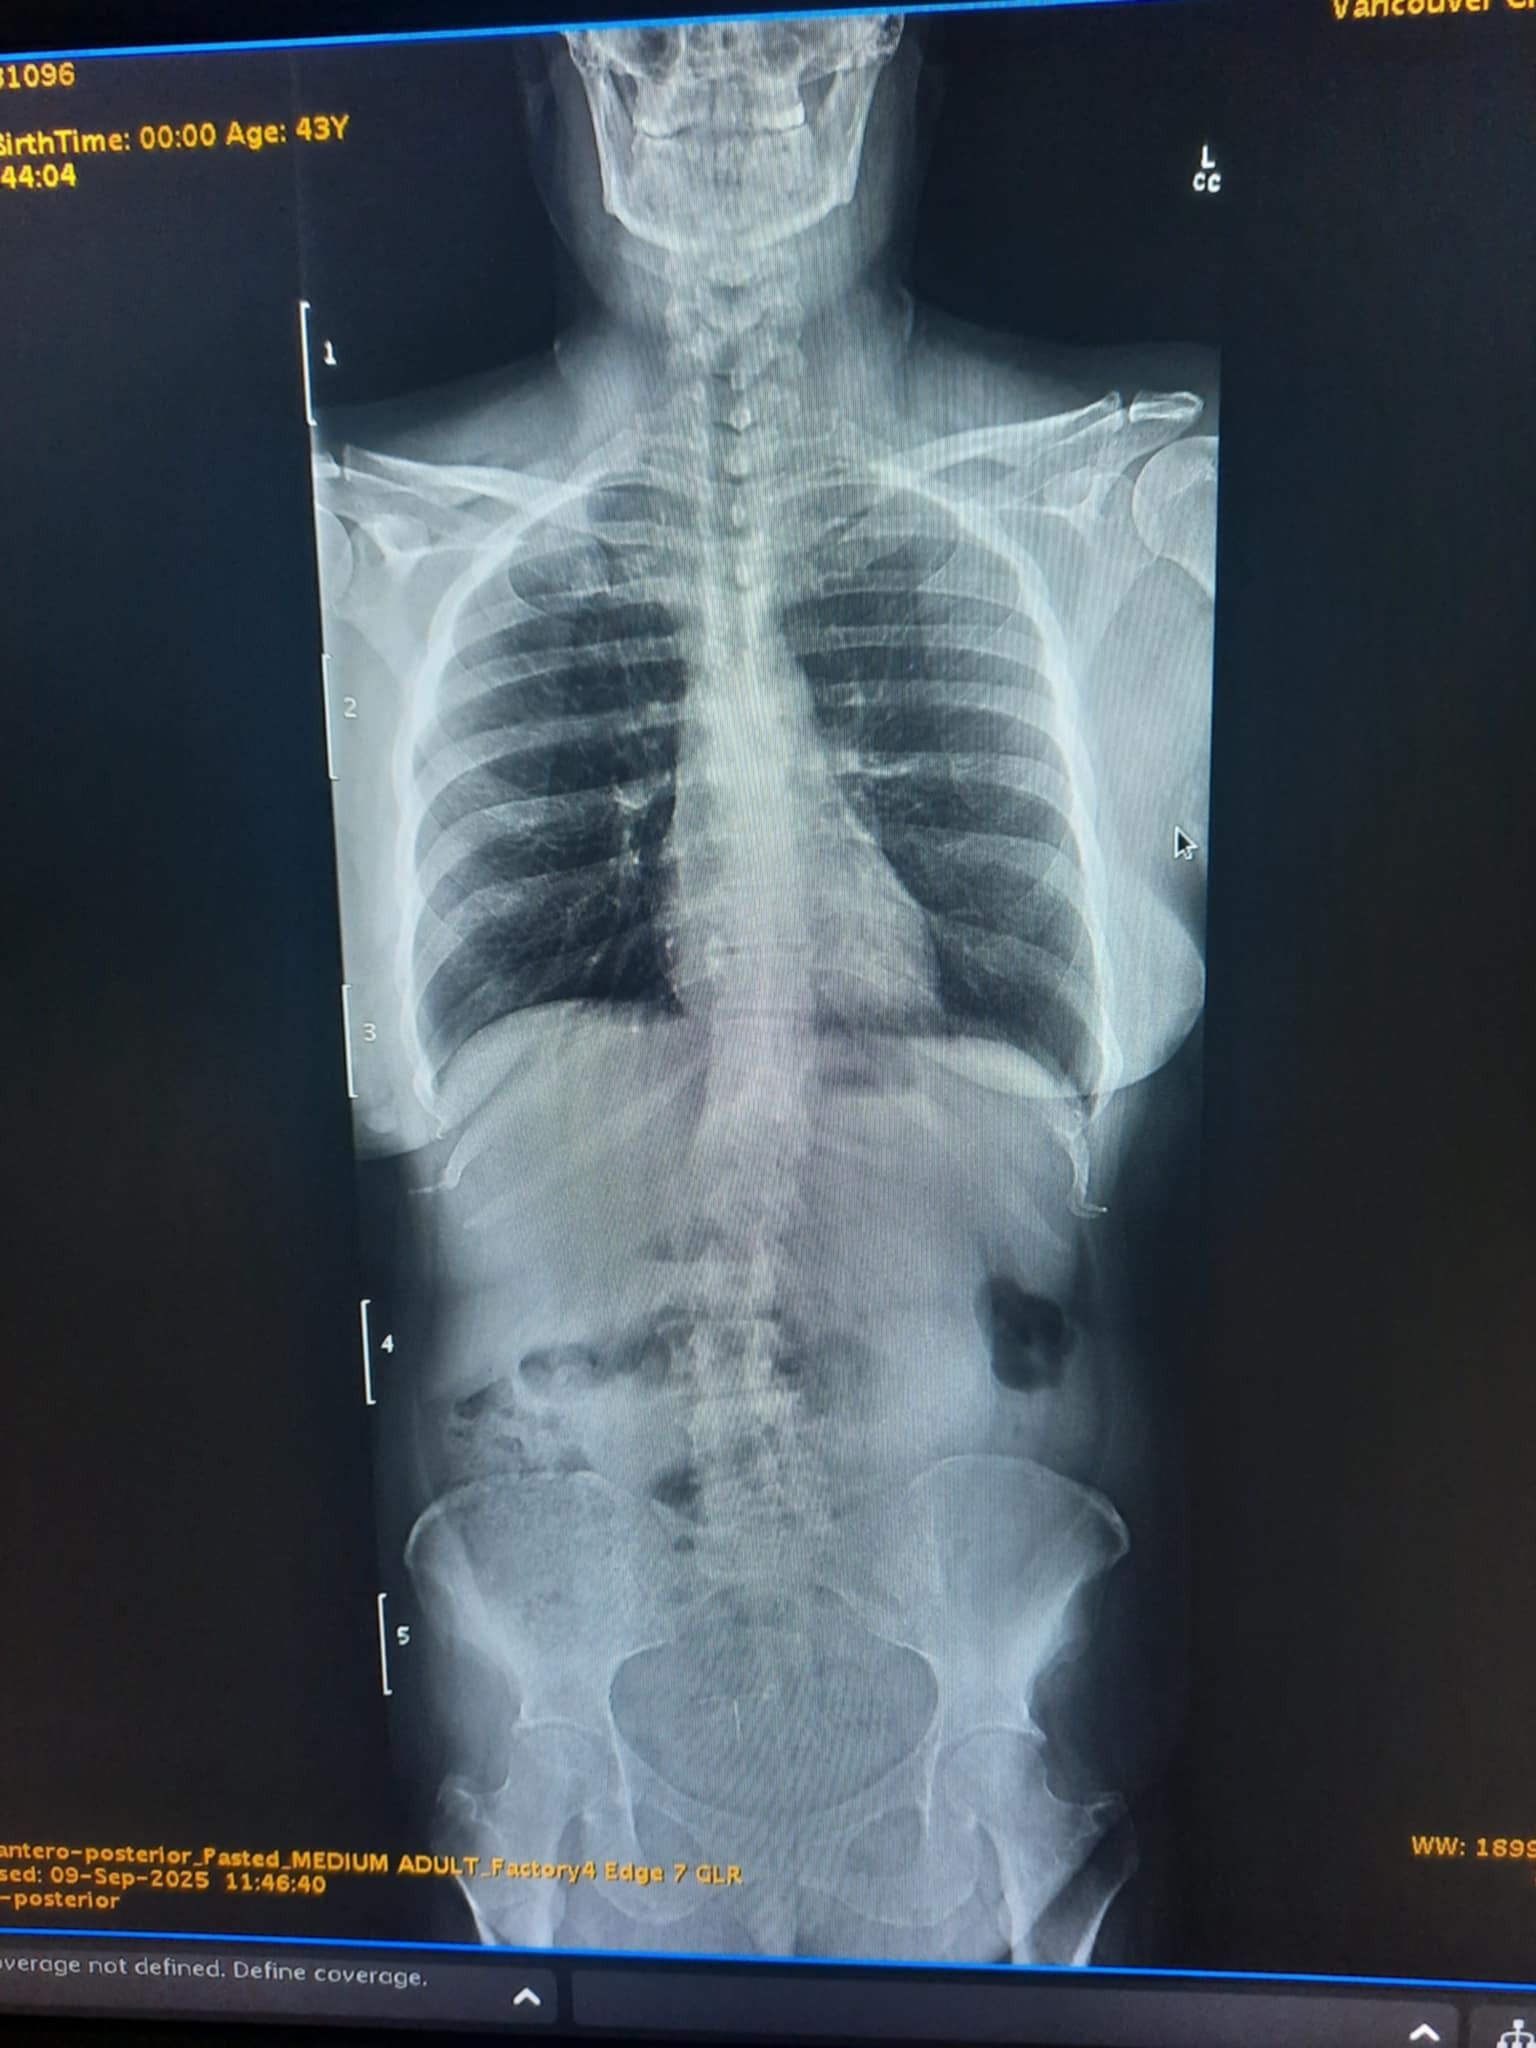

XRay indicates Double Curve (S-shaped) Scoliosis

Scoliosis Location: thoracic, and lumbar (dominant) regions.

9/9/2025-recomended for ALIF (anterior lumbar interbody fusion) Surgery for fusions of L2, L3, L4 & L5 with disc replacement between those (3 cages).